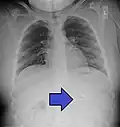

A coin seen on lateral CXR in the esophagus -